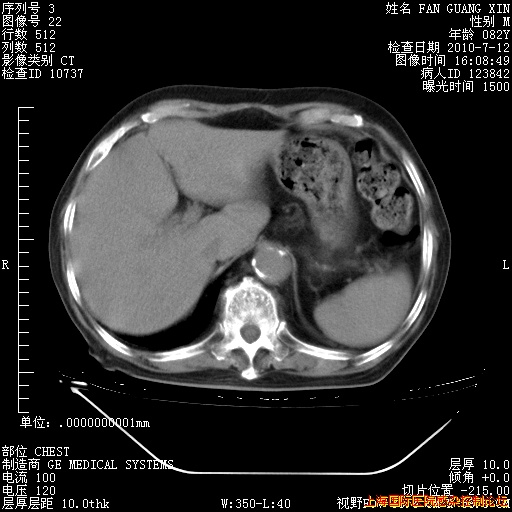

今天复查CT

今天CT

整整相隔30天的肺部CT好像有所好转啊。甲强龙减量第3天,需要观察体温。